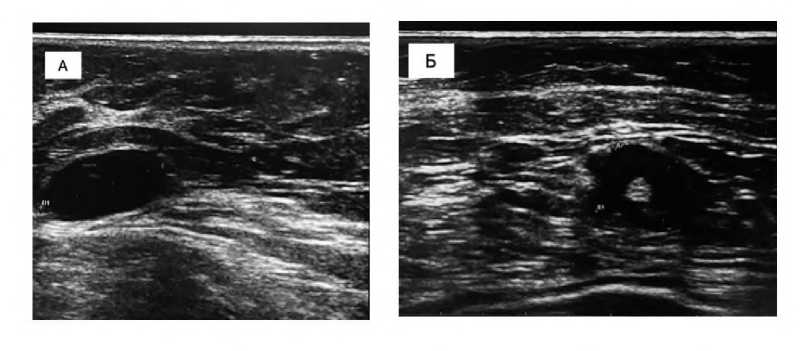

По данным ПЭТ-КТ от 05.2024: метаболически активное злокачественное новообразование с поражением правой молочной железы, правых подмышечных, надключичных и правых шейных л/узлов (Рис. 2).

Рис. 2. Серия аксиальных срезов ПЭТ шеи и органов грудной клетки (справа) от 13.05.2024. (А) Аксиальный срез ПЭТ шеи, отмечены увеличенные шейные лимфоузлы справа. (Б) Аксиальный срез ПЭТ органов грудной клетки, отмечены увеличенные надключичные лимфоузлы справа. (В) Аксиальный срез ПЭТ органов грудной клетки, отмечены увеличенные подключичные лимфоузлы справа. (Г) Аксиальный срез ПЭТ органов грудной клетки, отмечены увеличенные аксиллярные лимфоузлы справа.